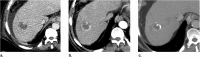

Computed tomography (CT) and magnetic resonance imaging (MRI) play critical roles for assessing treatment response of hepatocellular carcinoma (HCC) after locoregional therapy. Interpretation is challenging because posttreatment imaging findings depend on the type of treatment, magnitude of treatment response, time interval after treatment, and other factors. To help radiologists interpret and report treatment response in a clear, simple, and standardized manner, the Liver Imaging Reporting and Data System (LI-RADS) has developed a Treatment Response (LR-TR) algorithm. Introduced in 2017, the system provides criteria to categorize response of HCC to locoregional treatment (e.g., chemical ablation, energy-based ablation, transcatheter therapy, and radiation therapy). LR-TR categories include Nonevaluable, Nonviable, Equivocal, and Viable. LR-TR does not apply to patients on systemic therapies. This article reviews the LR-TR algorithm; discusses locoregional therapies for HCC, treatment concepts, and expected posttreatment findings; and illustrates LI-RADS treatment response assessment with CT and MRI.